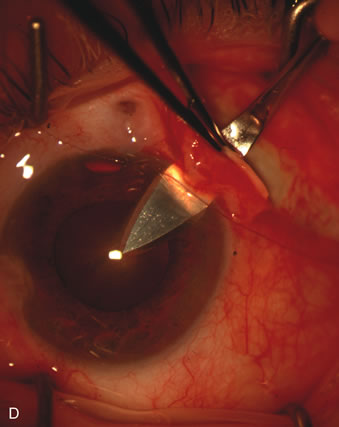

Fig. 1. The anatomic advantage of small incision cataract surgery for the glaucoma patient. A. Long-term bleb function with a large cataract incision is difficult to achieve with either ECCE-trabeculectomy or trabeculectomy followed later by ECCE. This bleb failed to form sufficiently when combined with large incision ECCE. The inflammation, bleeding, and long-term wound healing with stimulation of fibroblasts associated with this technique are more likely to cause bleb failure. In addition, the increased iris manipulation necessary to deliver the nucleus and subsequent iris repair adds to the long-term breakdown of the blood aqueous barrier. B and C. Two-site phacotrabeculectomy has the advantage of small incision cataract surgery combined with separate site trabeculectomy. The incision size is one third the size of the standard ECCE. The inflammation is less severe, and cataract wound healing is confined to the temporal area. Visual rehabilitation with phacoemulsification and foldable IOL is much faster. Phacoemulsification allows successful lens extraction even in the unfriendly environment of a smaller pupil compared with ECCE. The trabeculectomy is performed in an entirely different site, well away from the wound healing associated with temporal phacoemulsification. The likelihood of this filter functioning long-term is greater than with ECCE-trabeculectomy. D. The surgeon also has the option of single-site phacotrabeculectomy with foldable IOL. Both the lens extraction and trabeculectomy are performed through one small 3.5-mm limbal incision.